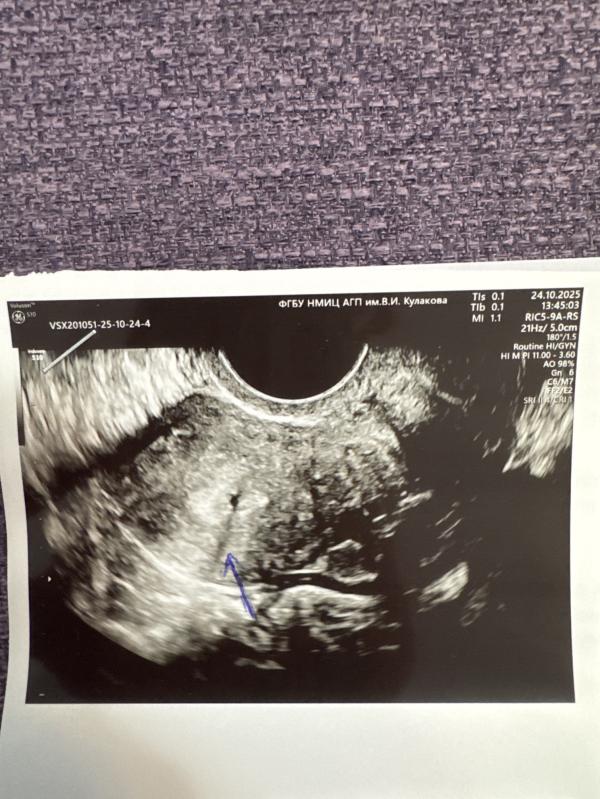

В заключение написано «в левом трубном углу тонкая синехия и мелкая анэхогенная зона – травматизация эндометрия»

Я просто обольстилась на то, что мелкая тонкая… но видимо придется гистеро делать